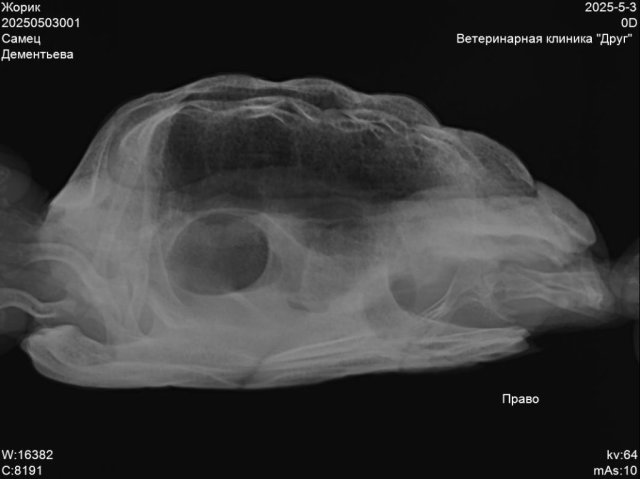

Пермь. Сухопутная черепаха. Террариум самодельный, длина 85см, ширина40, высота 40.лампа накаливания обычно работает в зоне прогрева 12часов.ультрафиолетовая лампа тоже 12часов    reptispa desert 10.0 uvb10. Грунт кокосовый субстрат перемешаный с речным песком. Температура под лампой 30-32гр.Летом кормим травой одуванчик, подорожник, клевер. Зимой салат, кабачок, огурец. Живёт у нас 9лет.вес 400гр., панцирь по длине 15см.заболела в конце марта. Чихала, был насморк, вялость. Лечили энрофлон аскорбинка, кальций, элеовит это было по рекомендации онлайн ветеринара. Потом еще назначали ингаляции с флуимуцилом это уже назначили в клинике друг, врач Бажина.Сейчас при еде выходит пена изо рта и носа.

20250503001_Жорик_Дементьева_20250503092325236.jpg

20250503001_Жорик_Дементьева_20250503092325086.jpg

20250503001_Жорик_Дементьева_20250503092324931.jpg

лечение когда закончили и снимки эти когда делали?

Лечение закончили в середине мая ингаляции с флуимуцилом. Рентген делали после лечения антибиотиком, перед лечением ингаляциями

@Галина М по-хорошему вам нужно снова на очный приём и делать новый рентген. Это очень сильная пена и даже если это из желудка - это очень не нормально. А из лёгких и подавно.